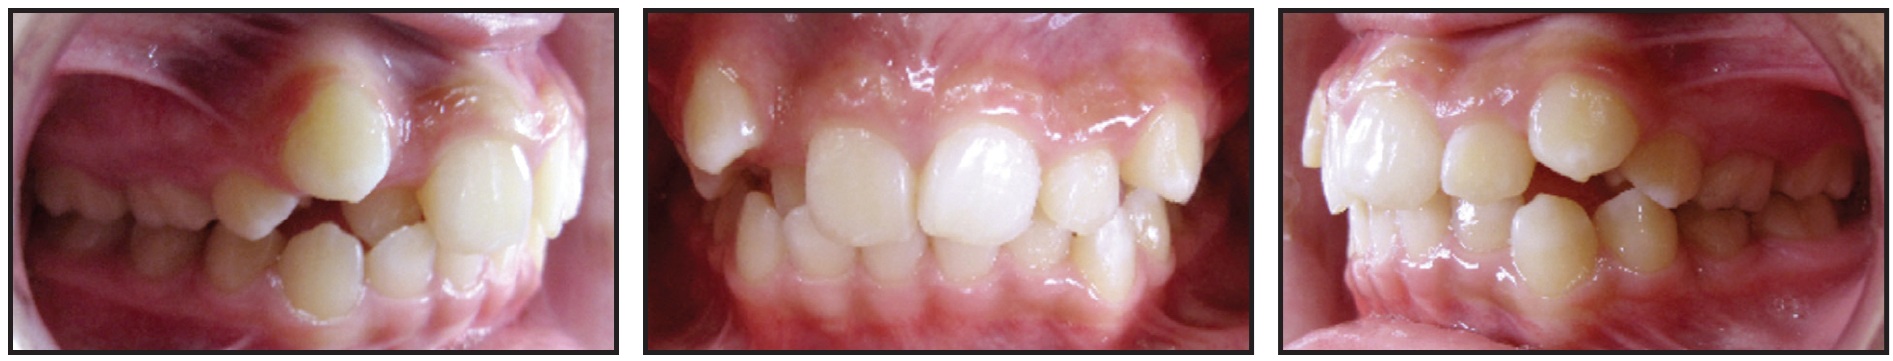

This patient presented with rotations from canine to canine in both arches (Fig. 5A). After 10 months of clear aligner therapy, the most severe rotation (the lower left lateral incisor) had been corrected, but a minor derotation of the lower right lateral incisor was still needed for ideal alignment (Fig. 5B). Even after an extra set of aligners, the rotation of the lower right lateral incisor was still unresolved (Fig. 5C).

Fig. 5 A. Patient with rotations from canine to canine in both arches before treatment. B. After 10 months of clear aligner therapy, minor rotation of lower right lateral incisor remaining. C. After extra set of aligners, rotation of lower right lateral incisor still unresolved.

Although premature contacts are easily ignored in an orthodontic practice, they can have serious effects on the tooth structure and support. Routine three-dimensional intraoral scans can easily show us where they are located. In this case, there was a strong contact between the upper right central incisor and lower right lateral incisor (Fig. 6). This contact should have been adjusted before more aligners were fabricated, but the premature contact with the distal marginal ridge of the upper right central incisor was clearly preventing derotation of the lower right lateral incisor (Fig. 7).

At this point, a selective occlusal adjustment was performed, and the rotations were entirely corrected with a few additional aligners.

It is not always possible to avoid premature anterior contacts due to the desired tooth positions or anatomy, the tooth-movement plan, or many other treatment-related factors. Nevertheless, occlusal contacts should be checked regularly in all cases. Every clinician should become familiar with the occlusal-adjustment techniques that will enable maximum intercuspation.